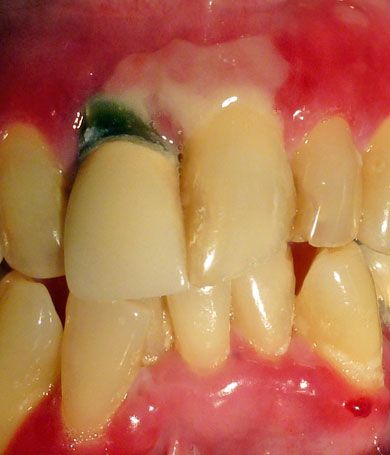

Figure 3

– A pseudomembrane above the maxillary central incisors was noted.